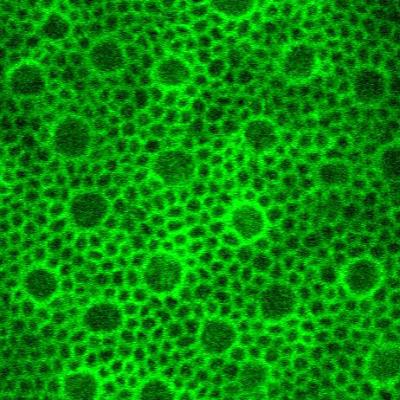

Retinal pigment epithelial cells imaged using artificial intelligence assisted imaging (P-GAN)

Retinal pigment epithelial cells imaged using artificial intelligence assisted adaptive optics optical coherence tomography imaging. Read the associated publication.